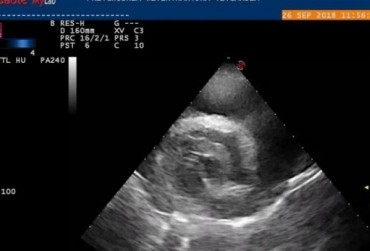

Metody małoinwazyjne w kardiologii weterynaryjnej. Czy chirurg jest jeszcze potrzebny? Opis przypadku

Artykuł przedstawia różne metody usunięcia worka osierdziowego. Prezentuje zarówno metody klasyczne, jak i małoinwazyjne, pokazując zalety i wady każdej z nich. Dzięki przedstawionemu opisowi przypadku pozwala zrozumieć, czym należy się kierować przy wyborze odpowiedniej metody operacji.